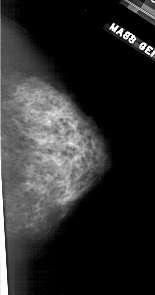

A_1709_1.RIGHT_MLO

RIGHT_MLO LINES 5491 PIXELS_PER_LINE 2611 BITS_PER_PIXEL 12 RESOLUTION 43.5 NON_OVERLAY